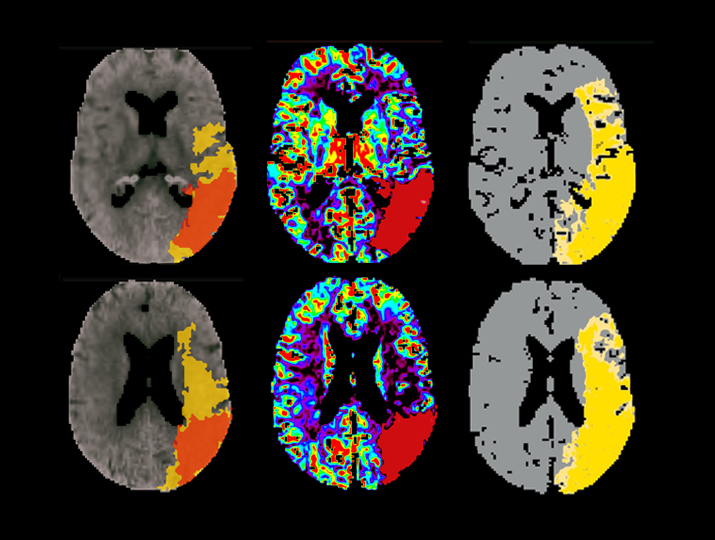

تحلیل کامل عصب-انکولوژی با تولید نقشههای کمی Perfusion، Diffusion و Permeability. قابلیت مقایسه طولی برای پیگیری تغییرات در تومورها و بیماریهایی مانند MS.